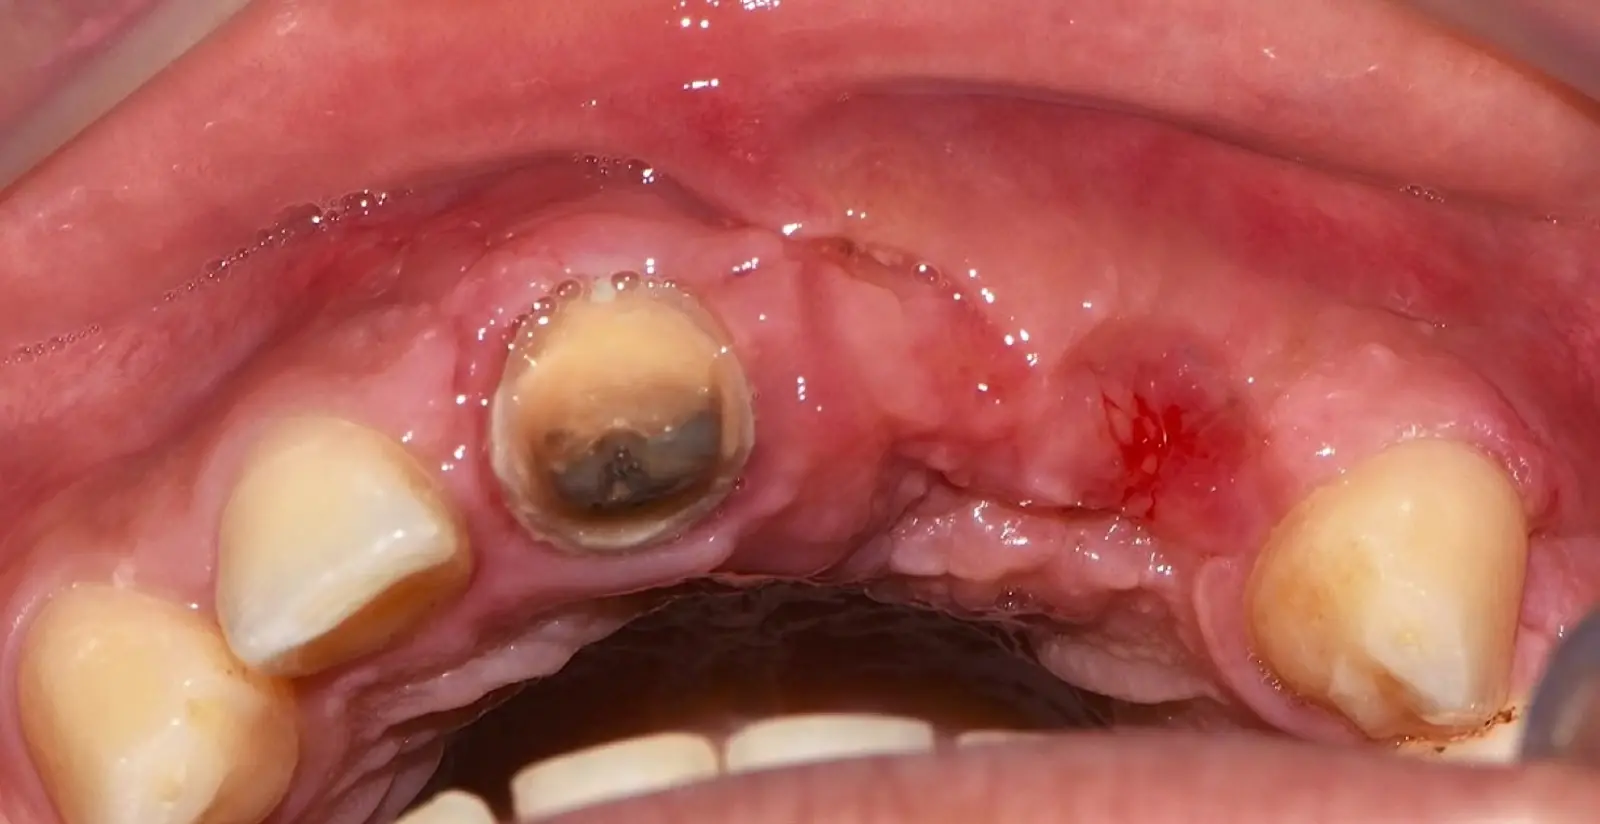

Los casos clínicos que presentamos a continuación muestran claramente las ventajas del piezoeléctrico en diversos procedimientos de terapia ósea regenerativa. En el primer ejemplo, una reconstrucción de reborde con injertos en bloque previo a la planificación de implantes dentales en un caso de edentulismo total superior con una severa reabsorción ósea. En el segundo ejemplo se utilizó esta tecnología para la reconstrucción de lechos para implantes de estructuras óseas con hueso en bloque de origen bovino y posteriormente la colocación de implantes dentales. Los dos casos son parte del capítulo 9 del libro “Cirugía piezoeléctrica: generalidades y aplicaciones clínicas”.